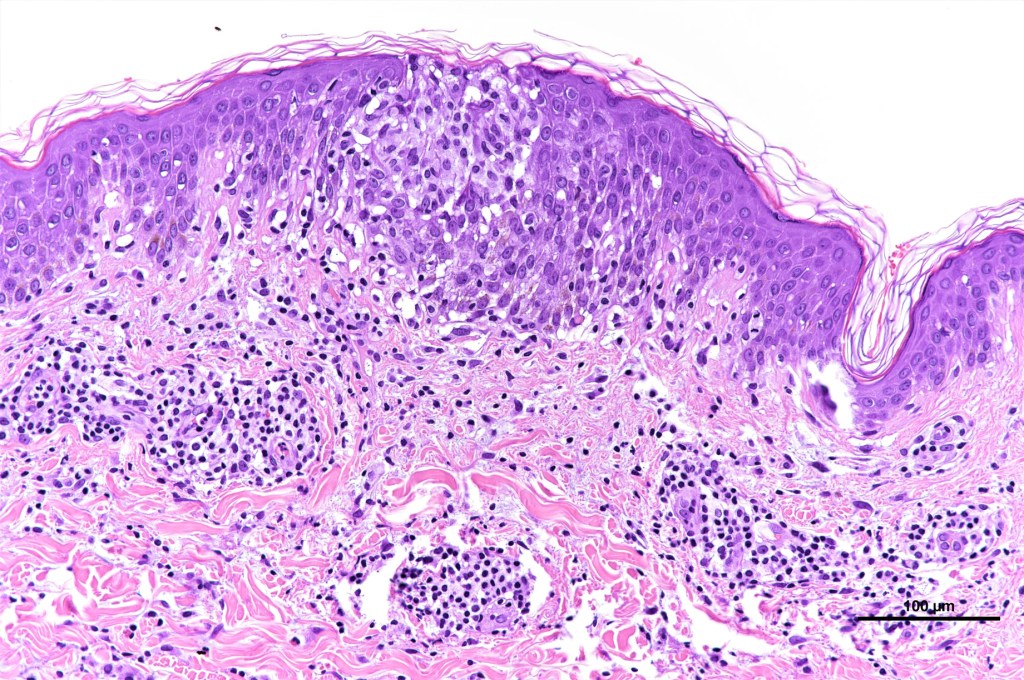

•Type A: 75-80%, wedge shaped infiltrate with base uppermost, large, anaplastic cells with abundant cytoplasm and vesicular nuclei containing prominent nucleoli, can resemble Reed-Sternberg cells, conspicuous mitoses & background infiltrate of lymphocytes, plasma cells, histiocytes, neutrophils & eosinophils

•Variable epidermal necrosis, epidermotropism, edema, hemorrhage & vasculitis/thrombosis